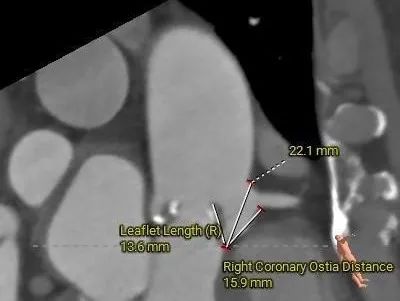

冠脉测量

冠脉开口高度可,切线角度测量,未见冗长瓣叶

• 冠脉开口高度尚可,切线角度测量,无冗长瓣叶;冠脉远端有钙化分布